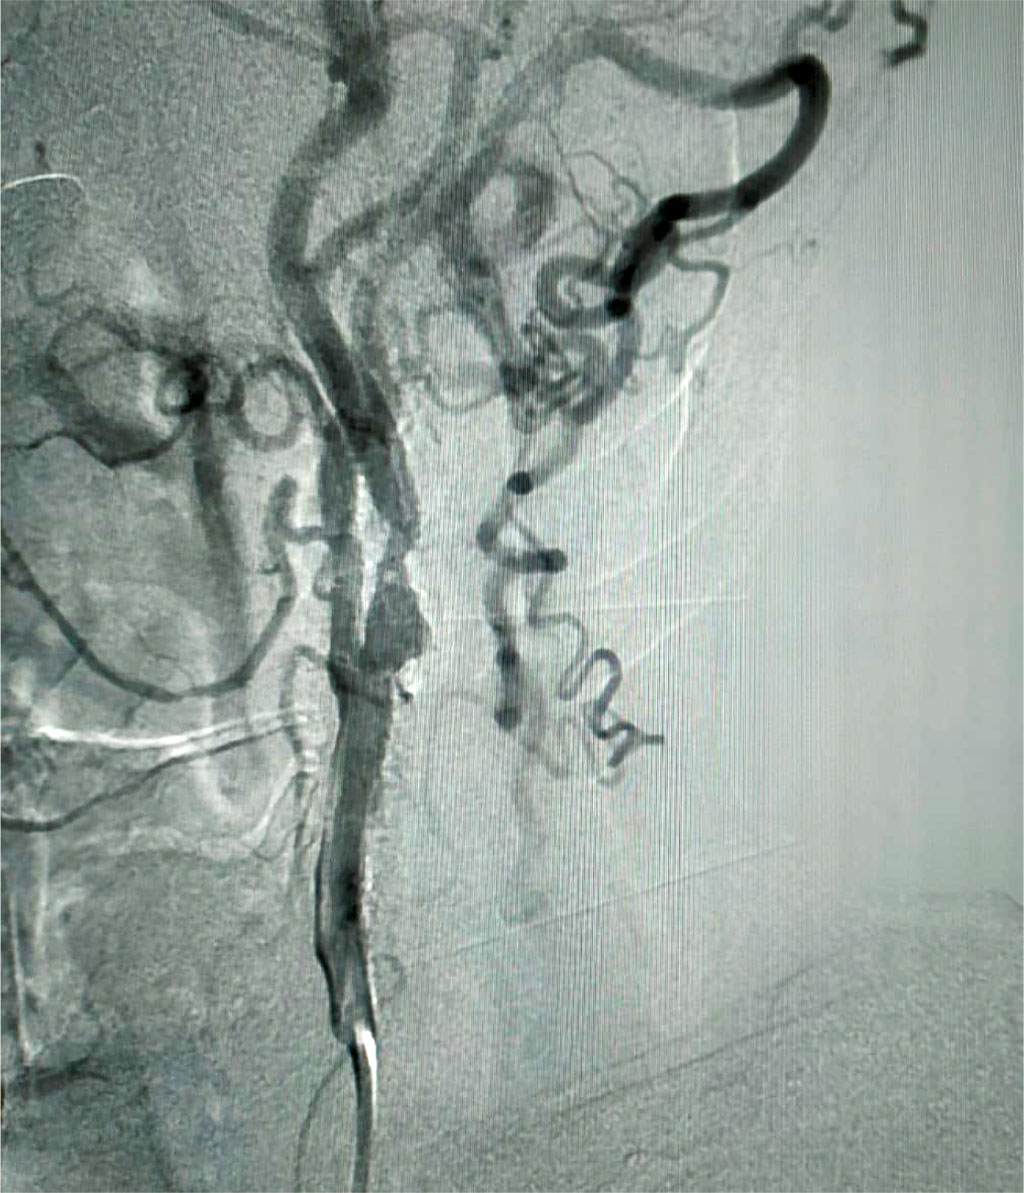

The purpose of the upcoming operation is to correct neurological deficits and prevent further development of strokes. Name of the operation: transluminal balloon angioplasty of the left internal carotid artery with stenting. Surgery protocol: under local anesthesia with Sol. Lidocani 2%-2 ml., the common femoral artery on the left was punctured and catheterized. A 6F introducer was installed and subsequently replaced with an 8F one. A guiding catheter was installed at the mouth of the common carotid artery on the left; a conductor with an Embosheld NAV6 filter was inserted beyond the stenosis site into the intracranial section of the internal carotid artery and opened. A 40 mm Protégé RX Tapered 10-7 self-expanding peripheral stent was implanted in the stenosis site. Next, postdilatation of the stenosis site was performed using a 20 mm RX Viatrac 14 Plus 6.0X balloon catheter with a pressure up to 10 atm. A control cerebral angiogram had no signs of malposition, proximal or distal dissection, and no distal embolism was detected. The tools were removed. A pressure bandage was applied. As a result of the operation, blood supply through the stented artery and pronounced collateralization on the right was restored. Fig. 2. Neurological status after surgical treatment showed significant positive dynamics. Consciousness is clear. No meningeal signs. Cognitive functions are preserved. D, S symptoms of oral automatism. Emotional lability is not detected. Pupils D = S. The reaction of the pupils to light is lively. The movements of the eyeballs are slightly limited outward. Convergence is weakened. Nystagmus and diplopia are not detected. Mild paresis and facial asymmetry. Pharyngeal reflexes are alive D = S. The tongue is in the midline. Paresis and sensory disorders are not detected. Tendon reflexes D>S. Babinski and Rossolimo signs are positive on the right side. Stable in the Romberg test. Coordination tests are successful. Pelvic functions under control.

Fig. 2. Carotid angiography. Condition after x-ray-guided endovascular stenting of the internal carotid artery on the left.